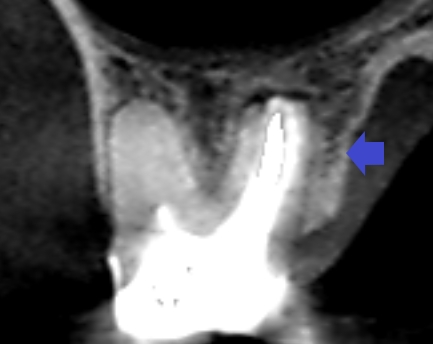

初診時の上顎第一大臼歯口蓋根の矢状断のCT画像です。

歯根の先端から横にかけて矢印のように長い影が認められ、歯根破折が疑われるケースでした。